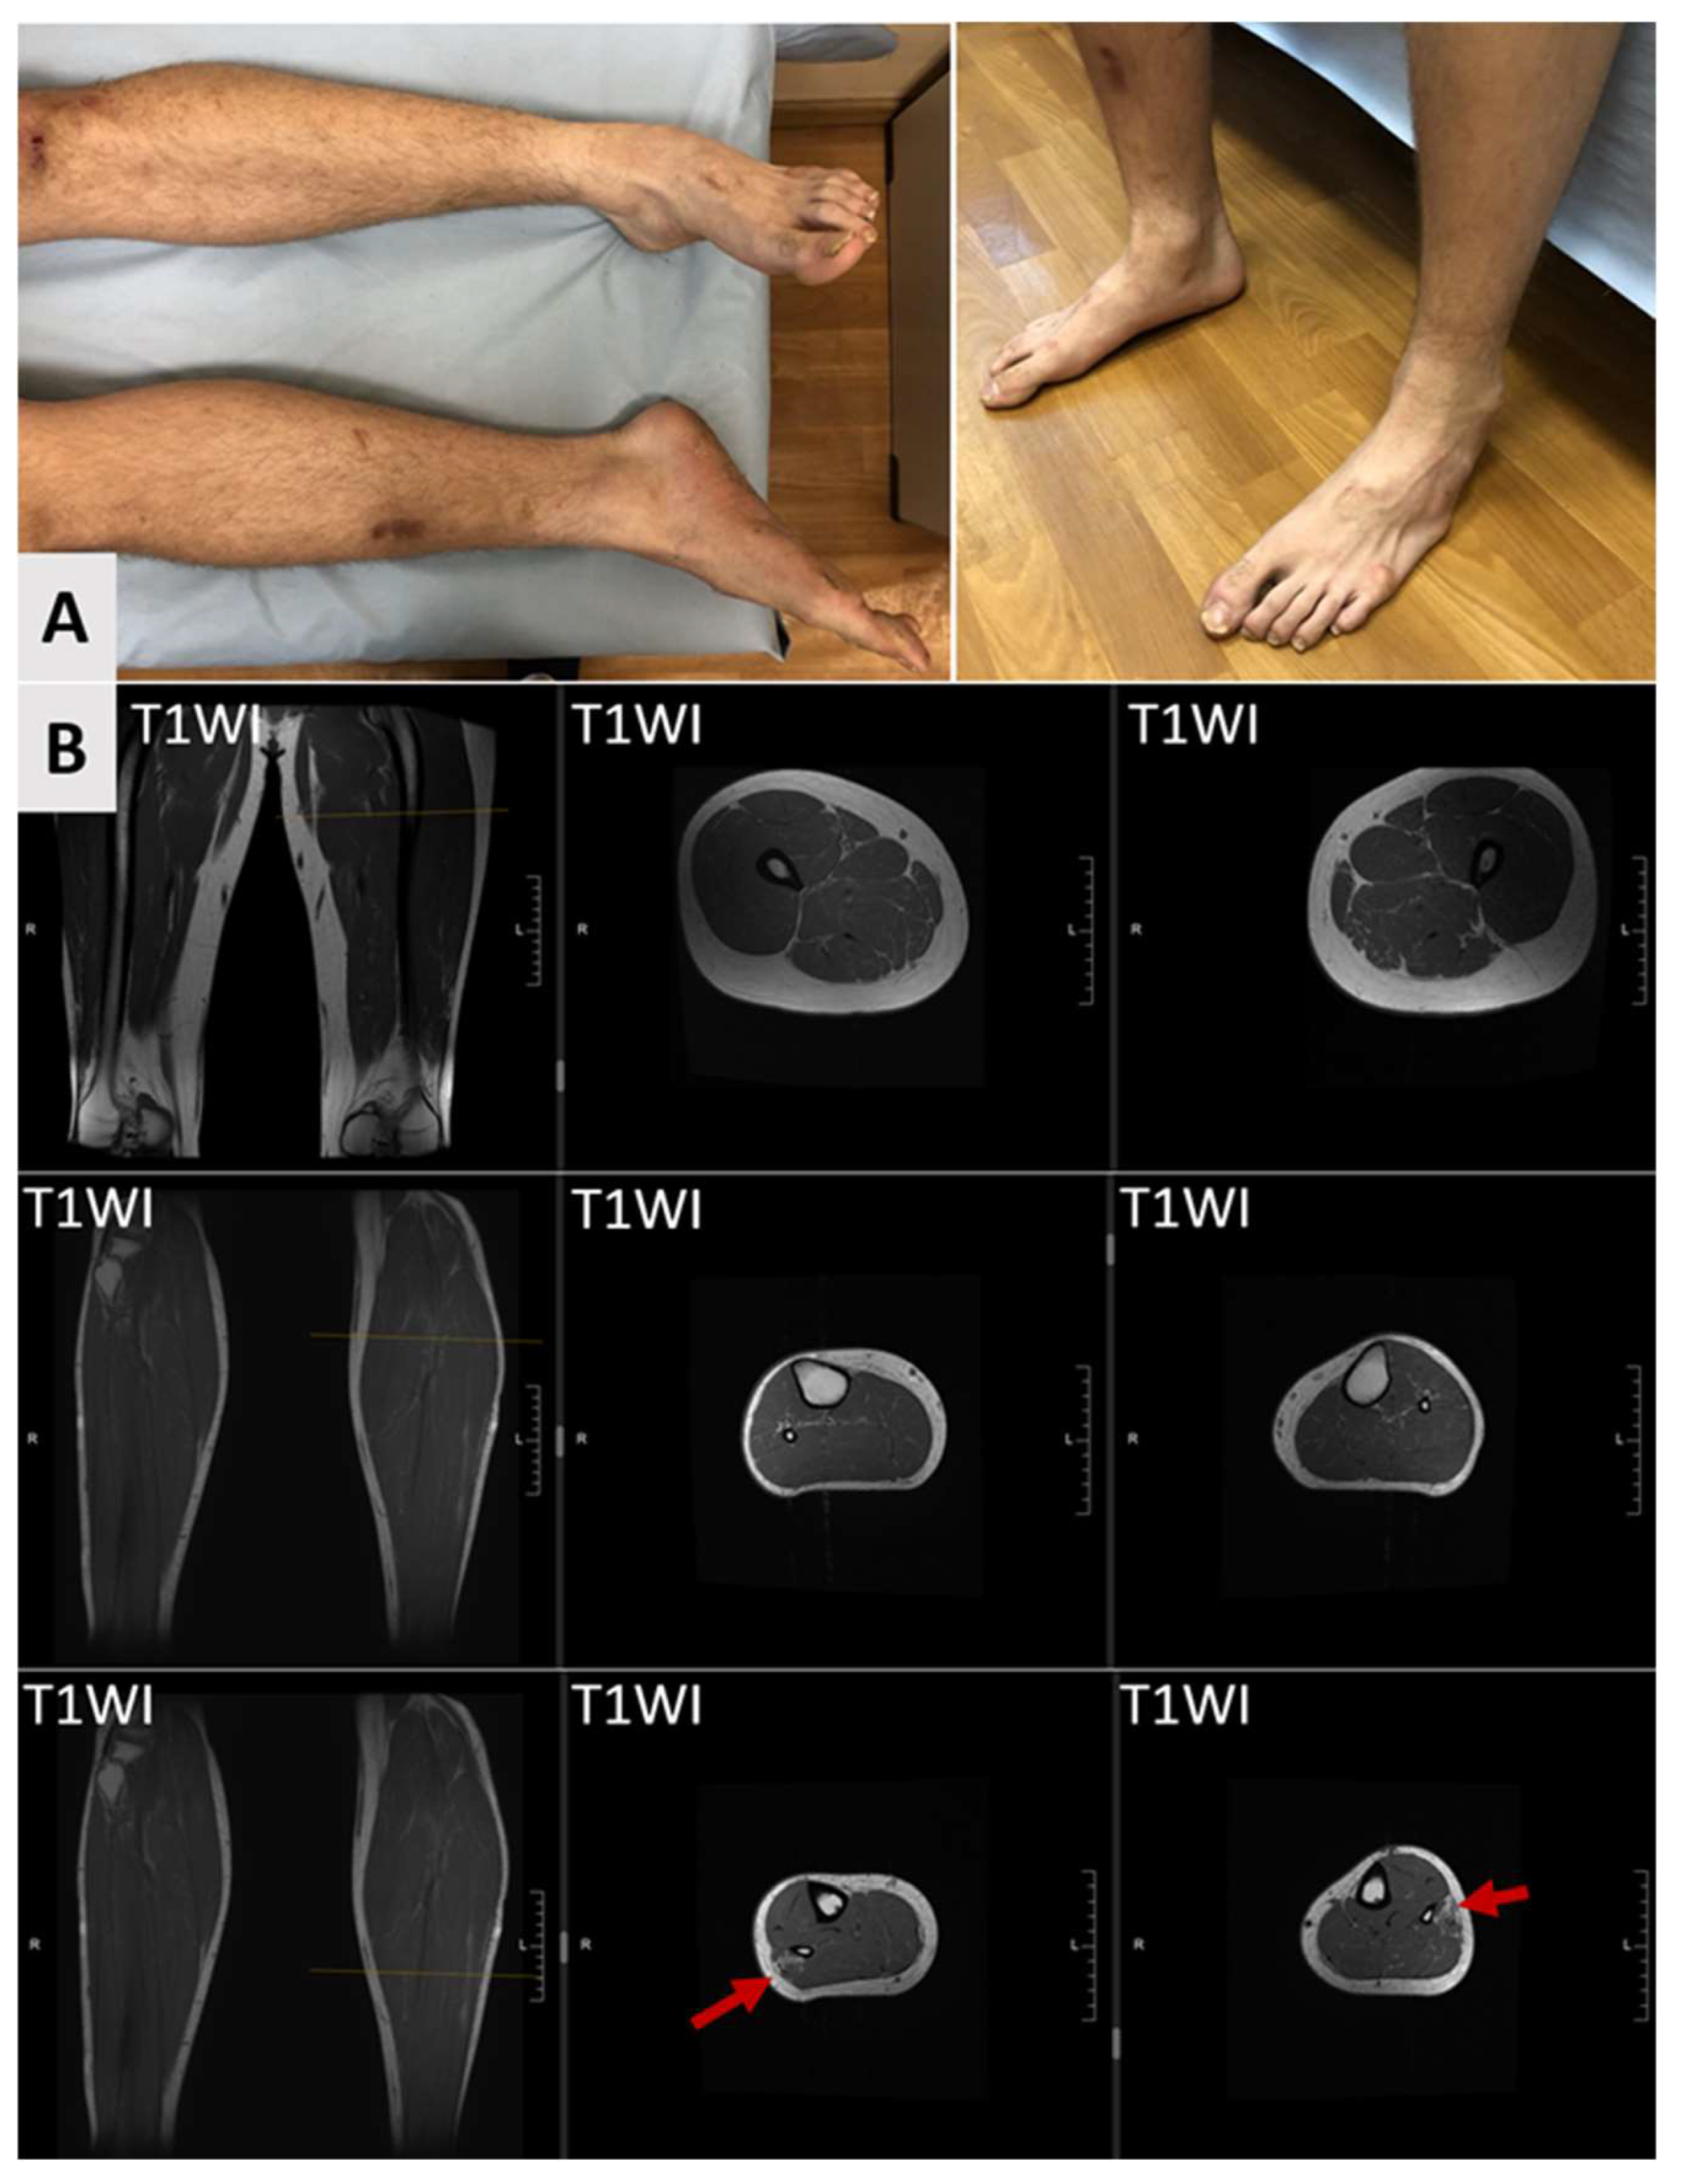

| Distal muscular hypotrophy/atrophy | 16% (5/31) |

| Foot drop | 23% (7/31) |

| Foot deformity | 42% (13/31) |